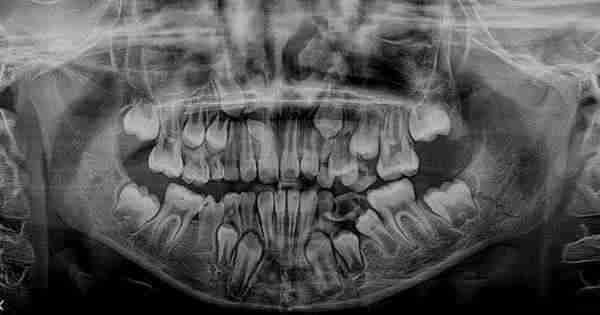

Los dientes supernumerarios son aquellos que salen de forma adicional a los que conforman el conjunto de piezas de la dotación dental normal. Dicho de otra manera, son los dientes extra a los 20 dientes de leche o a los 32 permanentes que conforman una dentadura común….